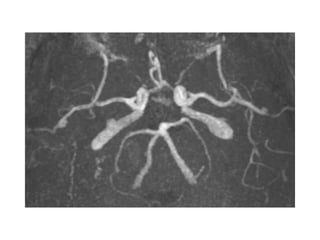

• Bilan neurovasculaire

– Monitoring FC et TA continu 24h/24

– Imagerie des TSA dans les 24 heures après l’admission

– Échographie cardiaque transthoracique +/- transœsophagienne

– Biologie: bilan lipidique, hémoglobine glyquée etc…

• Chirurgie vasculaire dans la semaine pour les sténoses serrées des